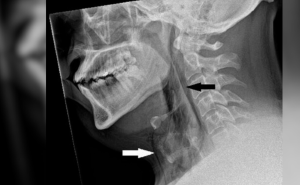

Boyun röntgeni, adamın cerrahi amfizem hastası olduğunu, yani havanın derinin altındaki en derin doku katmanlarının altında sıkıştığı bir durumu ortaya çıkardı.

Daha sonra bilgisayarlı tomografi (BT) taraması, yırtığın boynunun üçüncü ve dördüncü kemikleri veya omurları arasında olduğunu gösterdi. Göğüsteki akciğerler arasındaki boşlukta da hava birikmişti.

Yapılan tetkiklerde Hapşırma sırasında adamın nefes borusunda 0,08 inç x 0,08 inç (2 x 2 milimetre) boyutunda bir delik olduğu tespit edildi.